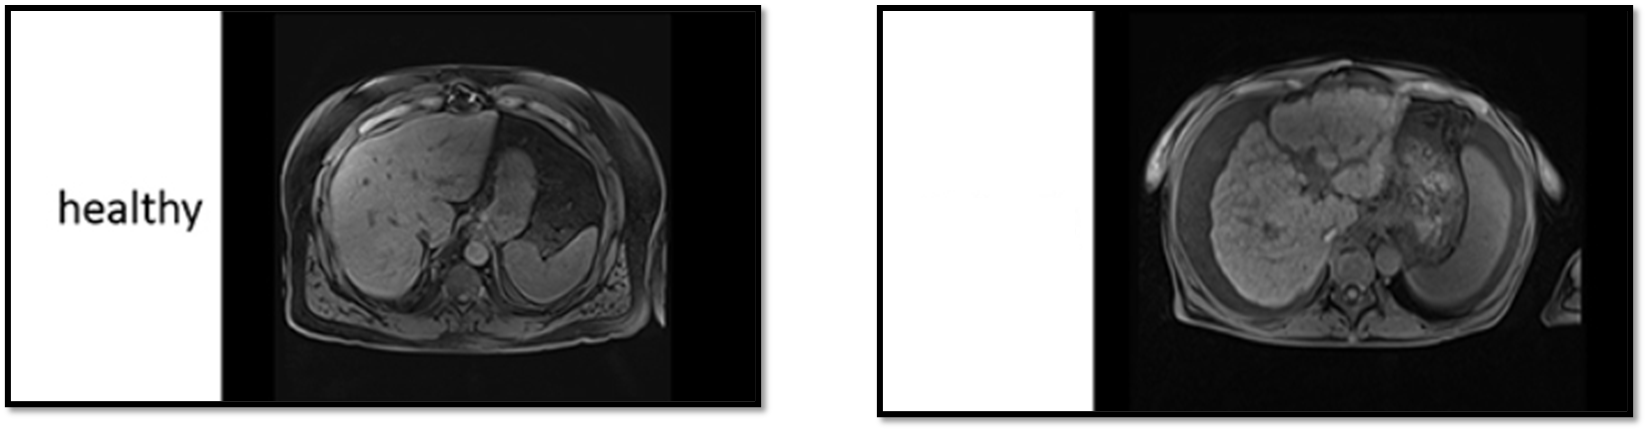

Hepatocellular Carcinoma (HCC)

______ is primary liver cell cancer.

It is most common in those with cirrhosis.

CT is modality of choice for diagnosis.

Hemangioma

An abnormal dense cluster of blood vessels.

Can be anywhere. Most common on the face, chest, back, and scalp.

Can be found in the liver.

Thought to be congenital.